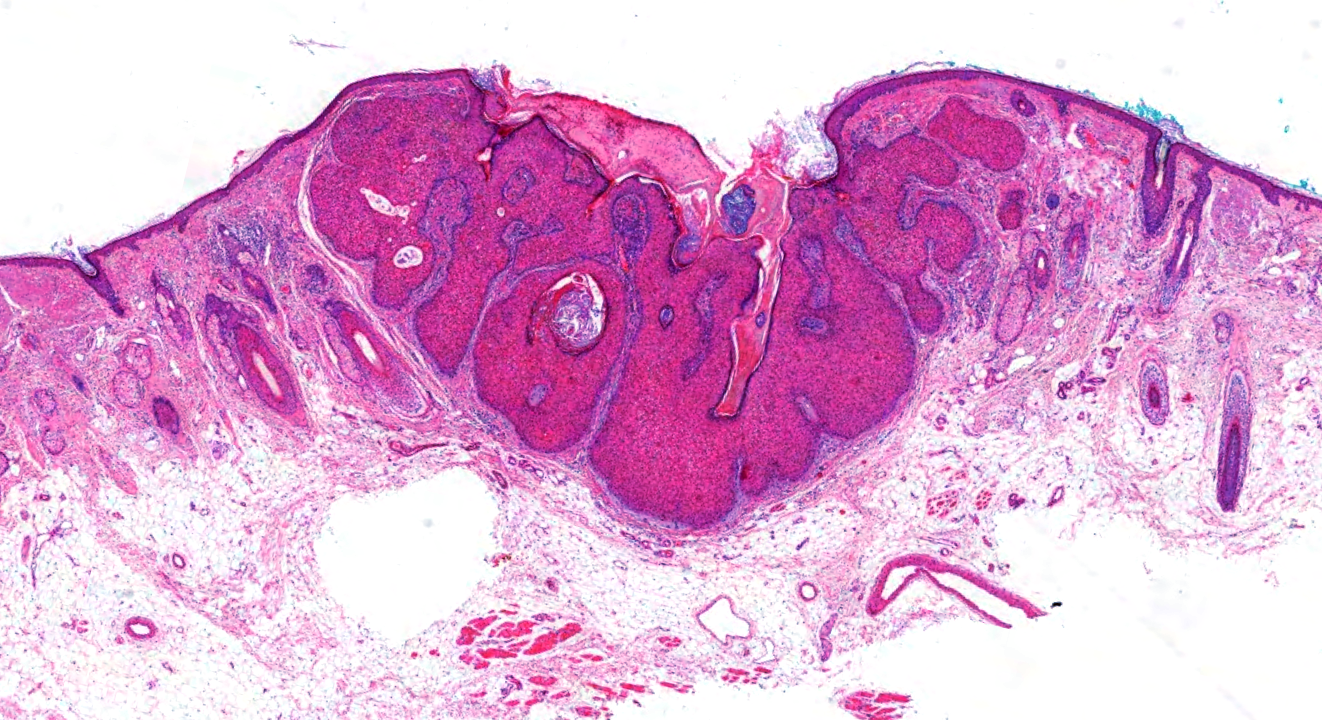

Dermatopathology Case 227 Get link Facebook X Pinterest Email Other Apps June 02, 2022 Solitary lesion on the upper lip of a 28 year old woman. Answer Get link Facebook X Pinterest Email Other Apps Comments